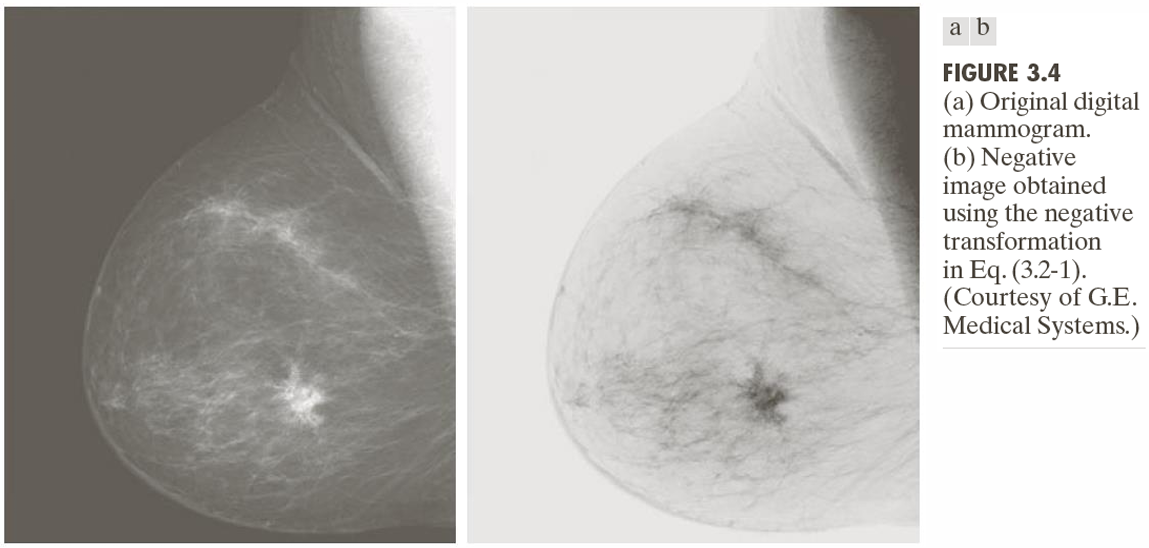

(2) Negative(영상 부정 변환)